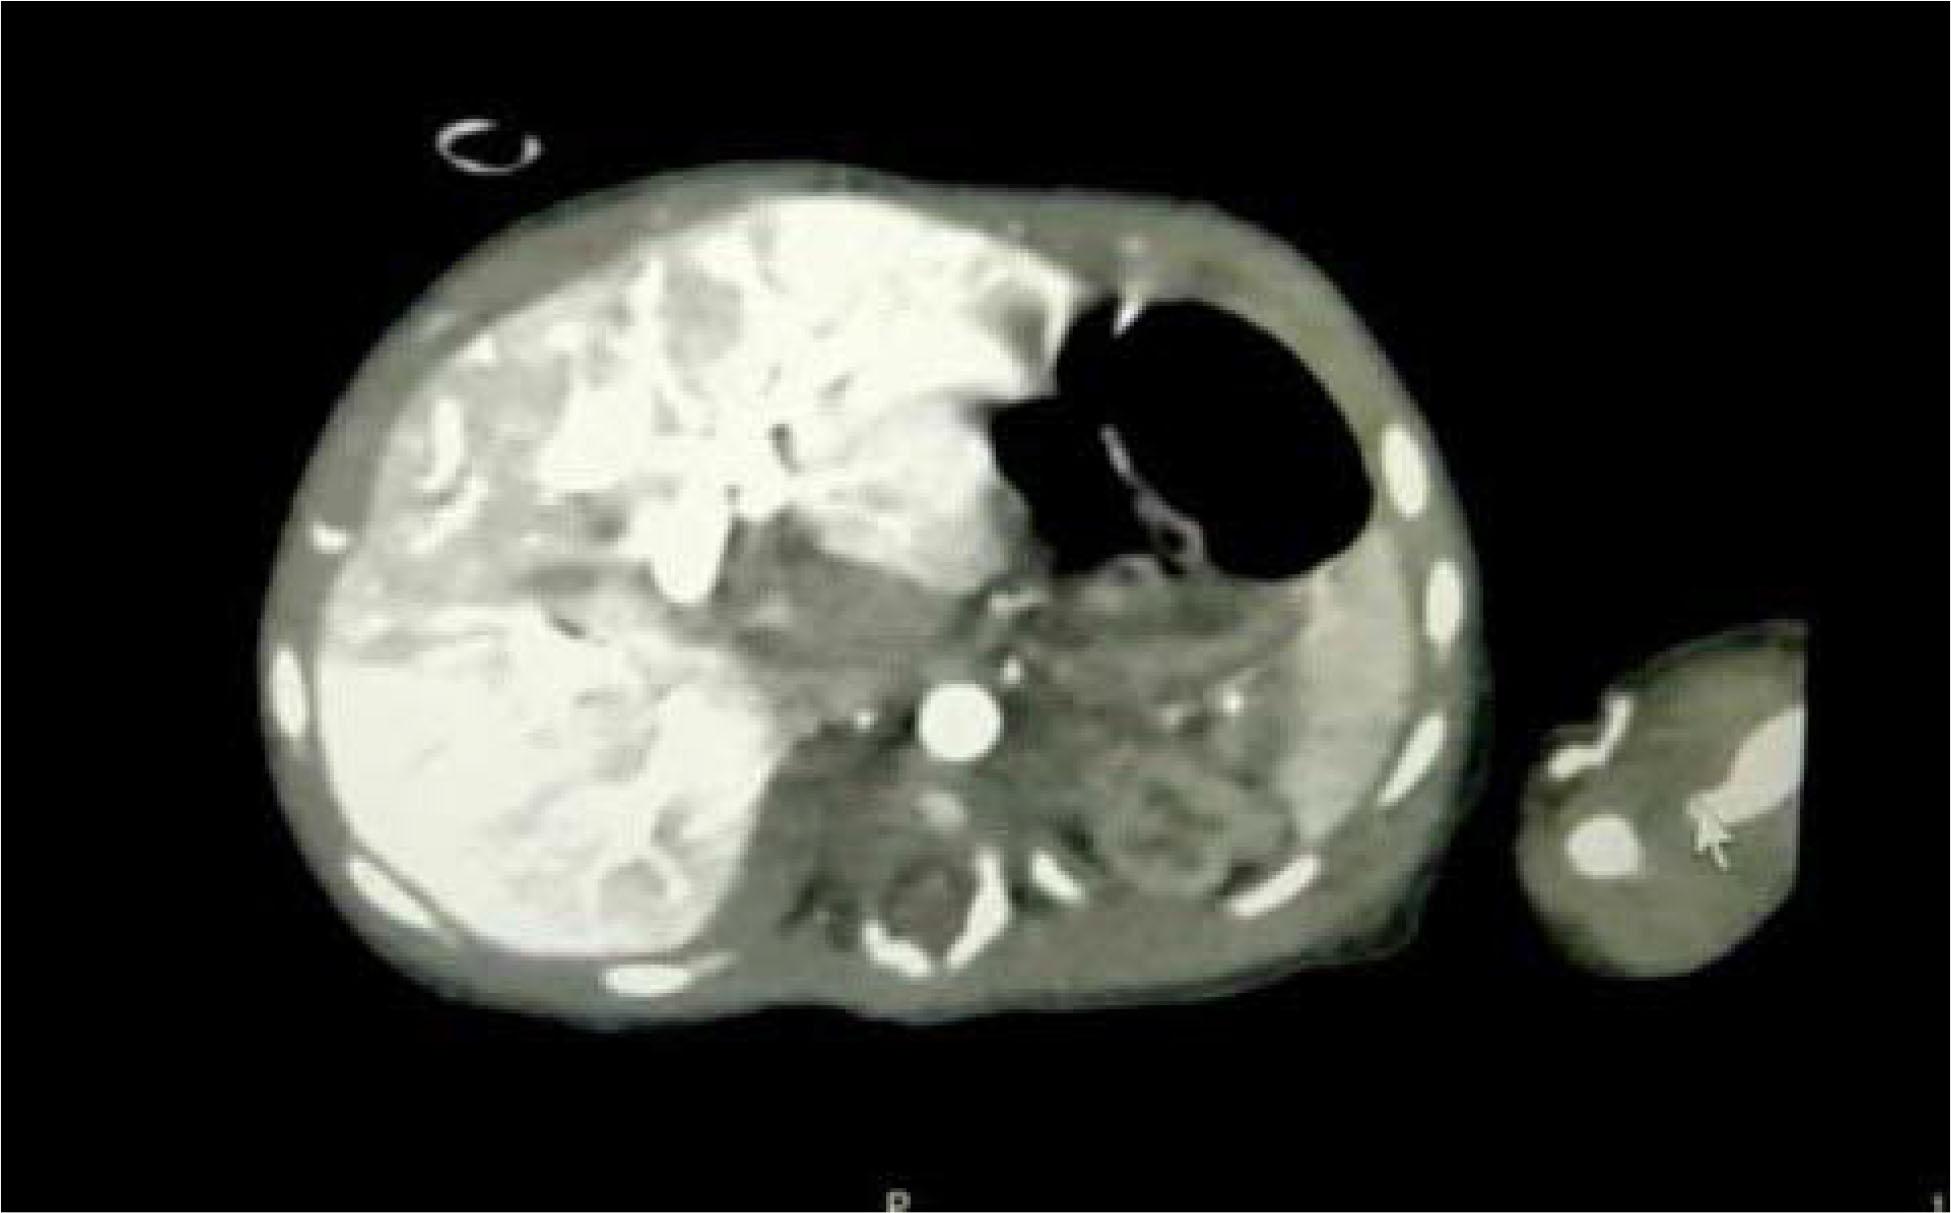

Figure 1

Contrast-enhanced CT scan showing early peripheral enhancement with central progression and central necrotic areas.